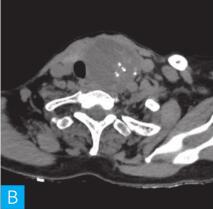

甲状腺CT检查:CT检查设备为256层iCT,病人采取仰卧位,扫描范围自外耳道平面至下颌角以下,常规扫描层厚为0.9mm、层间隔0.9mm,电压120kV,管电流280mA,矩阵512×512;经右肘静脉团注法增强扫描,碘海醇80ml,流速4ml/s,动脉期25秒扫描,静脉期60秒扫描。见图1。

图1 甲状腺CT

A、B.甲状腺CT横断面平扫;C~H.甲状腺CT横断面增强

答案C 解析:该病灶病史时间长,无发热及疼痛;病变位于一侧甲状腺,边界清楚;甲状腺血流及静态显像示:甲状腺左叶较大“凉”结节。因此不考虑恶性肿瘤及感染性病变。病变强化特点为结节状改变,呈现肿块样,故考虑肿瘤样病变。

CT平扫可见甲状腺左叶圆形以低密度为主病灶,大小为8.0cm×6.5cm,边界清晰,边缘尚光整,其内密度不均匀,低密度区CT值18HU,部分密度稍高,并可见斑点状粗大钙化影;CT增强后,甲状腺左叶病变呈不均匀渐进性强化,结节状改变,动脉期强化区CT值99HU,静脉期CT值85HU,且强化范围增大,提示该病变的血供较为丰富,应该考虑肿瘤样病变,结节性甲状腺肿可能性大。